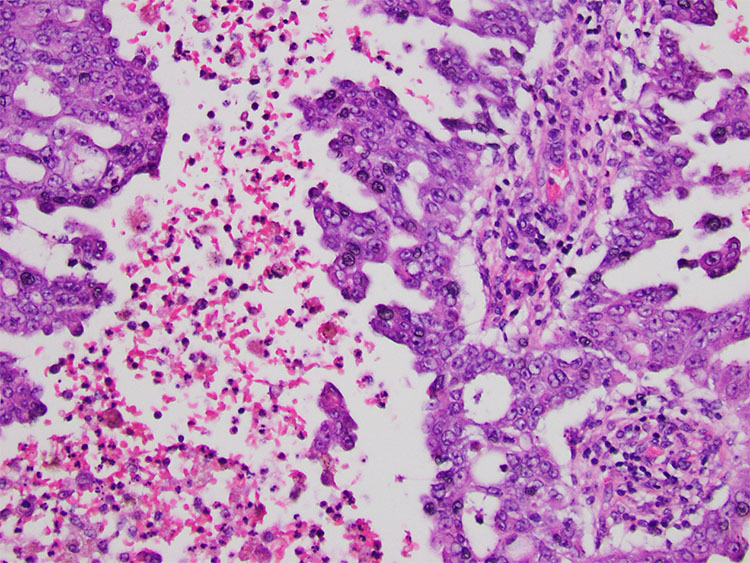

Grossly, the kidney had a 5 x 5 x 3.5 cm white-tan well-circumscribed homogeneous mass with soft, necrotic cut surfaces extending to the kidney capsule (Figure.1). Histologically, the tumor was composed of a mixture of reticular and cribriform growth patterns within a desmoplastic stroma (Figure 2-3). The tumor cells were pleomorphic with eosinophilic cytoplasm and hyperchromatic, enlarged nuclei with prominent nucleoli (Figure 4). Sickled red blood cells were also observed within vessels and the surrounding parenchyma. Immunostaining of the tumor showed positive staining for PAX8 and loss of expression of INI1 (Figure 5). The tumor was noted to invade the pelvicalyceal system with negative surgical margins but had metastasized to two of the twelve regional lymph nodes submitted.

Two months post-surgery, follow-up imaging showed liver lesions. Core needle biopsies of these lesions revealed tumor cells which were morphologically consistent with the primary renal tumor (Figure 6).